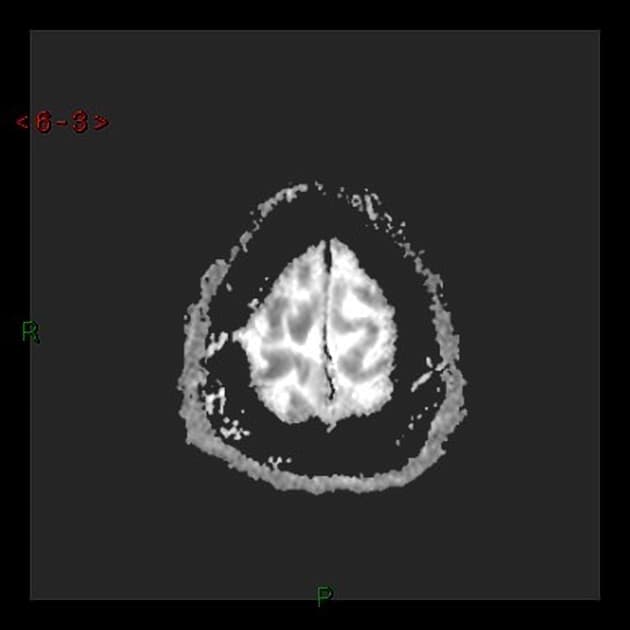

- Tăng tín hiệu trên hình ảnh T2/FLAIR kèm hạn chế khuếch tán rõ rệt, đối xứng hai bên, ảnh hưởng đến chất trắng, đặc biệt vùng trên lều (bán nguyệt phóng xạ, trung tâm bán nguyệt), cuống tiểu não giữa, và chi sau của bao trong, lan xuống đến cuống não.

- Các sợi U dưới vỏ được bảo tồn (nhận thấy rõ nhất trên FLAIR và T2).

- "Việc bảo tồn các sợi U dưới vỏ là đặc điểm hình ảnh quan trọng giúp phân biệt bệnh lý chất trắng do độc chất hoặc chuyển hóa với các bệnh mất myelin."

- "Tổn thương đối xứng hai cuống tiểu não giữa là dấu hiệu đặc trưng của độc tính thần kinh do fluorouracil."